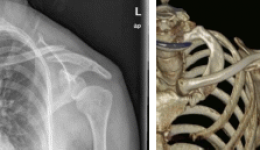

近日,茂名市人民医院创伤骨科团队成功运用“天玑”骨科手术机器人为一名左锁骨骨折的中年女性患者实施微创手术,这是该院创伤骨科团队运用骨科手术机器人进行术式创新的又一次成功尝试。前不久,41岁的患者梁姨在家中意外跌倒,本以为只是小伤,却...